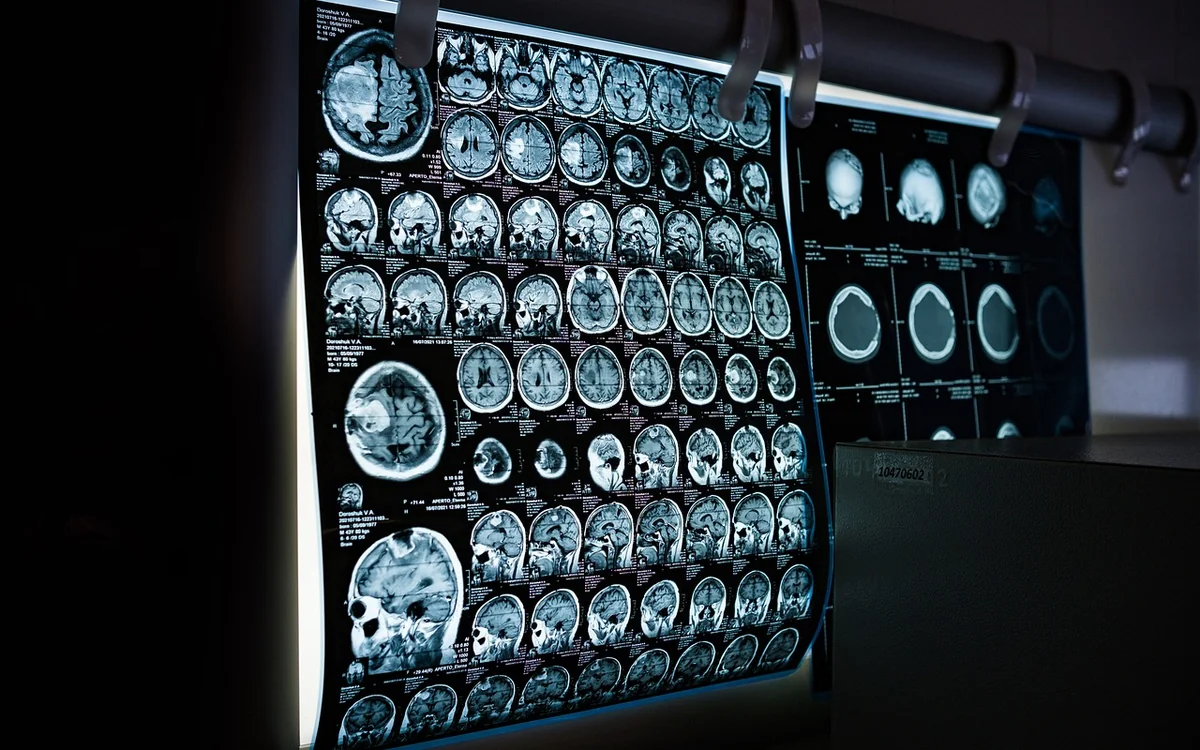

우리의 삶에서 뇌 건강은 매우 중요한 요소로 자리 잡고 있습니다. 치매는 단순히 노화의 결과로 여겨지지만, 최근 연구에 따르면 올바른 생활습관과 식단이 뇌 건강을 지키는 데 결정적인 영향을 미친다는 사실이 밝혀졌습니다. 따라서 치매 예방을 위해서는 뇌 건강 관리를 생활 속에서 실천하는 것이 필수적입니다. 특히, 젊은 세대에서도 발생하는 알코올성 치매나 ADHD와 같은 문제들은 주의력이 떨어지고, 뇌 기능에 부정적인 영향을 미칠 수 있습니다. 이러한 문제를 예방하기 위해 우리는 무엇을 할 수 있을까요?

치매 예방을 위한 뇌 건강 관리법은 사실 어렵지 않습니다. 건강한 식단, 규칙적인 신체 활동, 충분한 수면과 스트레스 관리가 핵심입니다. 이러한 요소들은 뇌를 활성화하고, 건강한 신경세포를 유지하는 데 필요합니다. 이번 글에서는 치매 예방을 위한 여러 가지 뇌 건강 관리법을 소개하고자 합니다. 작은 변화가 큰 효과를 가져올 수 있다는 사실을 기억하며, 오늘부터 실천해 보세요.